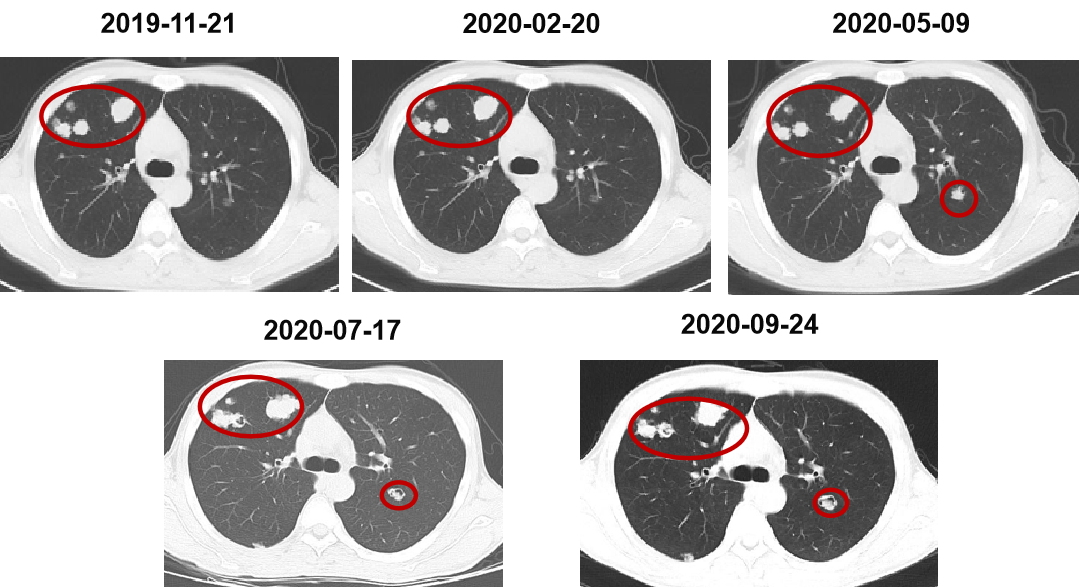

二 病例分享 专家简介 01 基本情况 刘某某,男性,28岁。 主诉:大便次数增多2月。 首诊时间:2018-07-03,北京大学人民医院。 既往史:右踝关节骨折术;痔疮病史。 个人史:无特殊。 家族史:其父为小细胞肺癌患者。 入院查体:ECOG 1分,无明显阳性体征。 02 初诊病史 肿瘤标志物:CEA 19.45 ng/ml。 肠镜及病理:直肠(距肛门约8cm处),直肠腺癌。 胸腹盆增强CT:1.双肺多发结节,考虑转移瘤可能性大;2.肝S6段异常密度灶;3.下段直肠癌可能性大。 盆腔增强MRI:(中位)直肠癌、T(3b)、N(2b)、癌结节(0)、CRM(阳性)、EMVI(阴性)、非区域淋巴结(阴性)。 上腹部增强MRI:肝S6段小结节,不典型血管瘤可能大。 初步诊断: 1.直肠癌(cT3N2bM1aIVA期 )肺转移; 2.痔疮; 3.右踝关节骨折术后; 4.肝血管瘤。 03 治疗方案 外院:XELOX。 我院首诊:2018-07-18。 免疫组化:MLH1(+),PMS2(+),MSH2(+),MSH6(+)。 2018-07-25至2018-09-26 XELOX *2+局部放疗*25f,PD。 基因检测(2018-10-23):KRAS、NRAS、BRAF基因均未见突变。 二线治疗:2018-10-18至2019-03-01 贝伐珠单抗+FOLFIRI*9 (SD→PD)。 疗效评估 三线治疗:2019-03-28至2019-07-23 西妥昔单抗+伊立替康+雷替曲塞*6(SD→PD)。 疗效评估 2019-07-25 瑞戈非尼 80mg po。 2019-09-26 复查:SD,瑞戈非尼 120mg po。 2019-11-21 复查:PD,瑞戈非尼 160mg po。 疗效评估 2019-12-19 至2020-09-24 信迪利单抗 200mg q3w +瑞戈非尼80mg po d1-d21 q4w。 2020年 ASCO 更新的瑞戈非尼+纳武利尤单抗(regorafenib+nivolumab)在晚期结直肠癌或胃癌患者中的Ib期临床试验(REGONIVO, EPOC1603)。 疗效评估 2020-09-26 盆腔增强MRI:直肠癌治疗后复查,与2020-05-10 MRI比较:直肠壁增厚程度较前似进展;直肠下段偏左侧新发不规则异常信号,考虑瘘管/脓肿形成。 考虑直肠下段脓肿,行抗感染治疗。 并于 2020-10-14 在气管插管全身麻醉下行腹腔镜下乙状结肠造口术。 2020-11-06 至2021-02-05 信迪利单抗200mg q3w+呋喹替尼3mg d1-21 q4w。 双肺多发转移瘤,对比 2020-11-04 CT较前增大、部分空洞形成。 TAS-102:新型口服细胞毒性药物 2021-V1版NCCN指南和2021 CSCO指南推荐更新:TAS-102±贝伐珠单抗(Bev)作为mCRC三线标准治疗。 2021-02-05 至今 TAS-102 60mg bid d1-5,d8-12,q4w 联合信迪利单抗200mg q3w。 不良反应 西妥昔单抗:皮疹; 瑞戈非尼:手足综合征; PD-1抑制剂:免疫性甲状腺炎; TAS-102:骨髓抑制(中性粒细胞IV度下降、贫血)。 04 诊疗小结